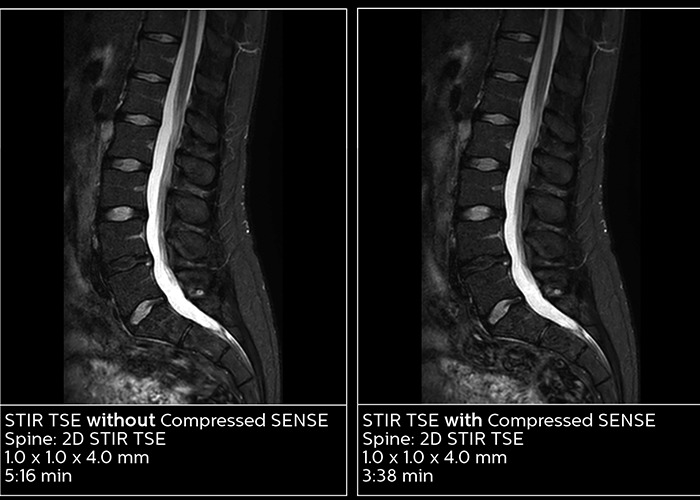

Utilizing MR in the emergency department means a prioritizing speed to enable a quick diagnosis. However, accelerating scans can compromise imaging quality and can result in blurry images. Through Compressed SENSE, an application that enhances productivity in imaging by increasing the data that is able to be pulled quickly from scans, including both 2D and 3D scans, all anatomical contrasts and all anatomies.